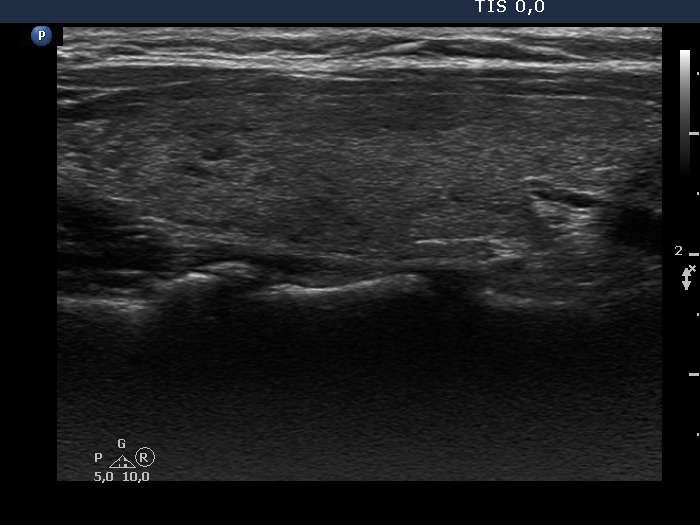

Consecutive patients with the final diagnosis of Hashimoto's thyroiditis - case 29 (496) (ultrasonographic picture 2)

Right lobe, longitudinal scan.